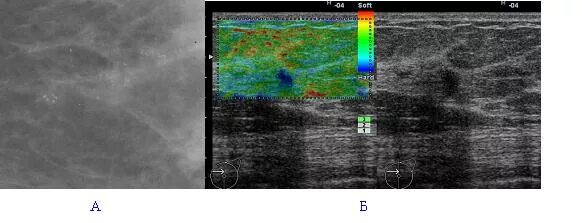

Протоковая карцинома маммография. протоковая карцинома молочной железы. протоковая карцинома на узи. протоковая карцинома молочной железы на узи.

Внутрипротоковая карцинома узи. внутрипротоковая карцинома in situ. протоковая карцинома молочной железы на узи. протоковая карцинома in situ молочной железы.

Внутрипротоковая аденокарцинома молочной железы рентген. инфильтративная протоковая карцинома.. инфильтративная протоковая карцинома молочной железы. внутрипротоковая карцинома in situ молочной железы узи.

Внутрипротоковая карцинома. протоковая карцинома молочной железы на узи. протоковая карцинома маммография.

Внутрипротоковая карцинома узи. фиброаденома молочной железы мрт. внутрипротоковая папиллома маммография. внутрипротоковая папиллома молочной железы мрт.

Внутрипротоковая карцинома узи. внутрипротоковая фиброаденома узи. внутрипротоковая киста молочной железы. внутрипротоковая карцинома молочной железы на узи.